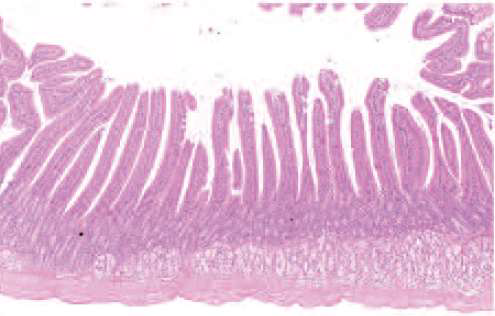

Stomach

9. CapsulaStomach

1

2

3

4

51. Mucosa,

2. Submucosa,

3. Muscularis,

4. Fibrosa,

6. Parietal cell,Stomach

Duodenum

41. Villi (cross-cut),

2. Lamina propria,

3. Glands,

4. GlandsIleum